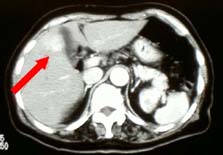

腹部超音波、ヘリカルCT |

肝臓がん |